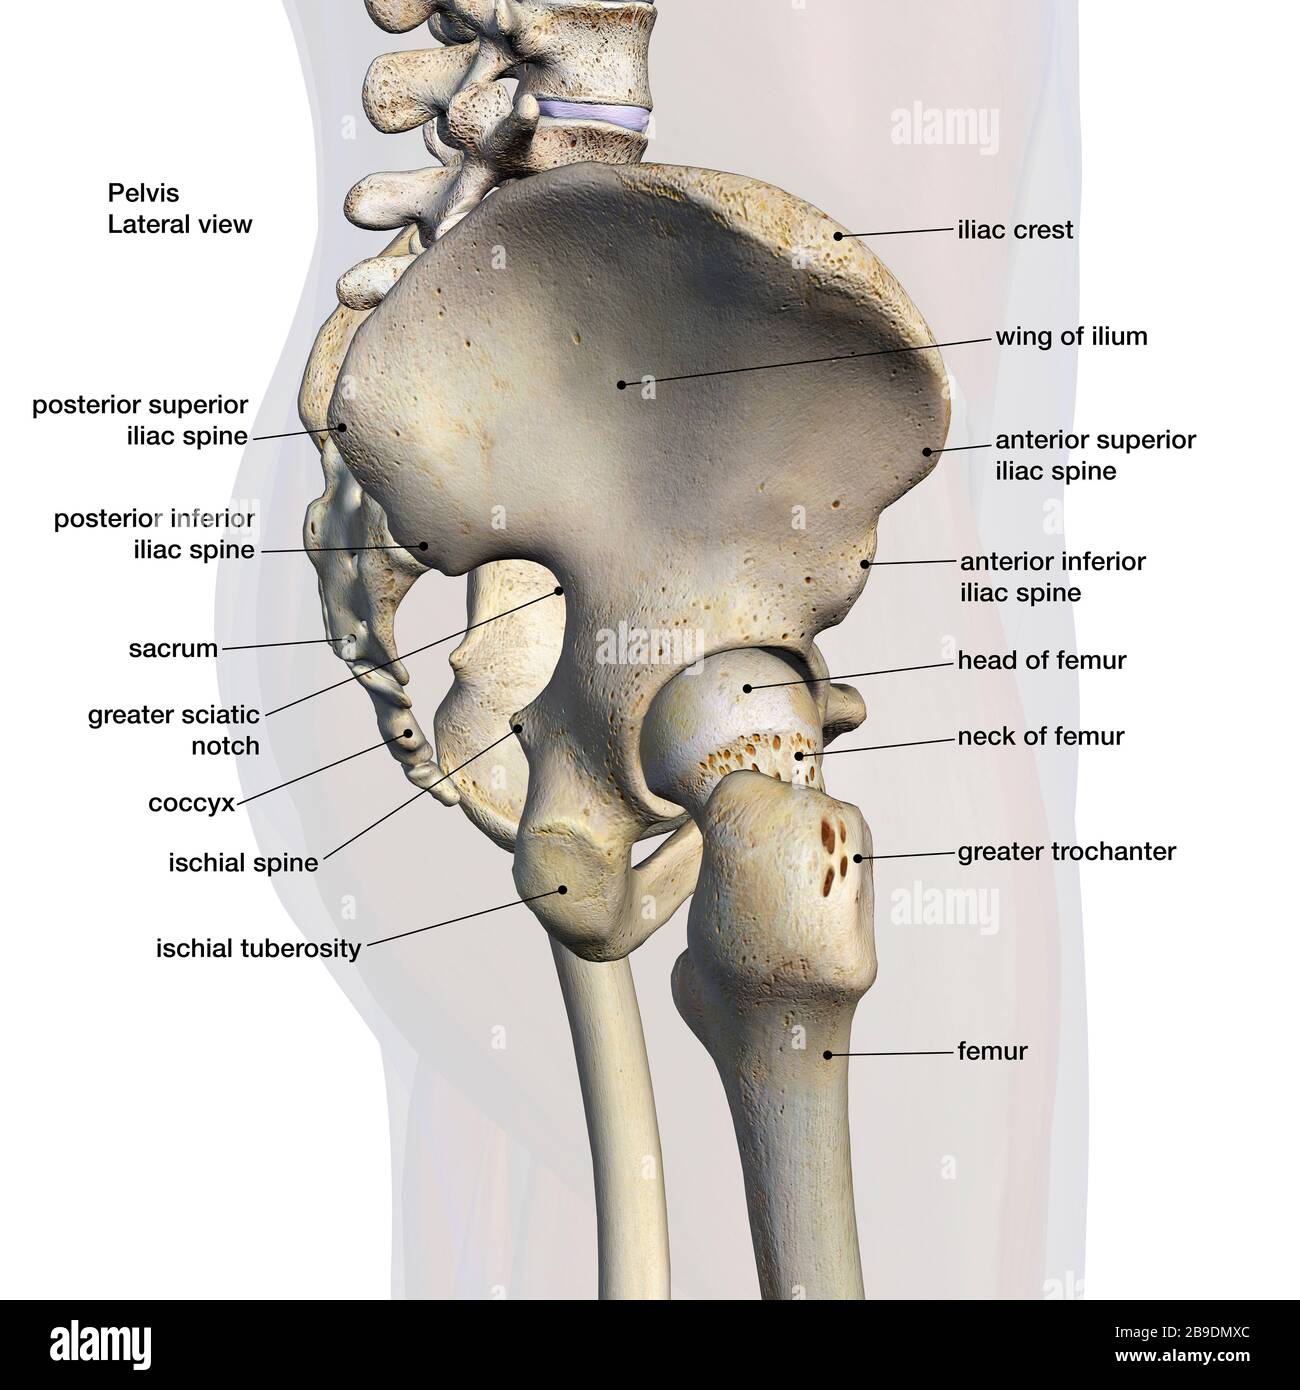

RFHT54Y0–Männliche Anatomie. Skelett und hervorgehobenen Lungen. 3D Illustration. Clipping-Pfad enthält.